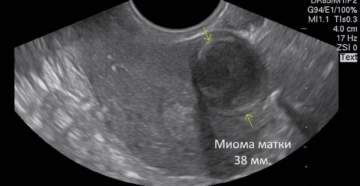

Размер миомы матки в неделях Миома матки представляет собой опухоль доброкачественного характера, появляющаяся в детородном…